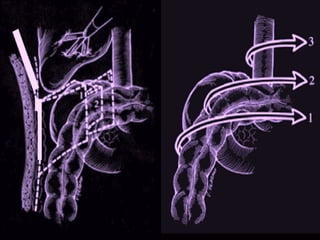

LIGADURA DO PEDICULO VASCULAR

ABORDAGEM DO PEDÍCULO